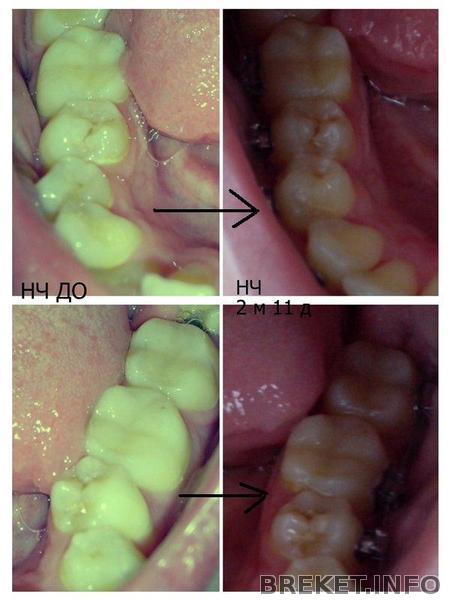

ВЧ И НЧ КОЛЛАЖ ИЗМЕНЕНИЙ

Таких ракурсов я еще не постила

Для удобства восприятия сделала стрелочки переходные))

На НЧ с одной стороны даже виден зуб мудрости, который мне потом удаляли))))